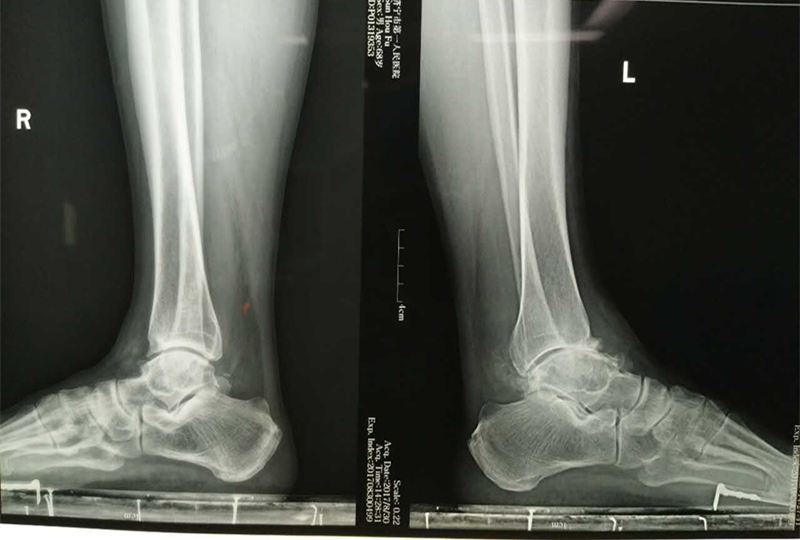

患者孙先生左踝关节疼痛已经8年多,加重伴肿胀及活动受限已经半年多。曾多次就诊诊断为“踝关节骨关节炎”,并予以针灸及药物等治疗,效果欠佳。手术前,患者已经不能独立行走,严重影响生活质量。为了通过手术彻底治疗,患者来到济宁市第一人民医院手外科足踝外科住院治疗。

踝关节置换术在医学界为难度较高手术之一。这也是鲁西南地区首例Inbone全踝假体置换术。该手术的成功开展标志着医院治疗终末期踝关节炎的水平再上新台阶。回顾世界足踝外科历史,全踝关节置换术目前历史约30到40年左右,因踝关节自身的解剖生理条件制约,踝关节承重大,但是动作幅度又相比膝关节、髋关节灵活,手术难度较高。从该手术方式发明至今,一直因手术技术和假体材料制约未能像其他关节置换术那样广泛开展。